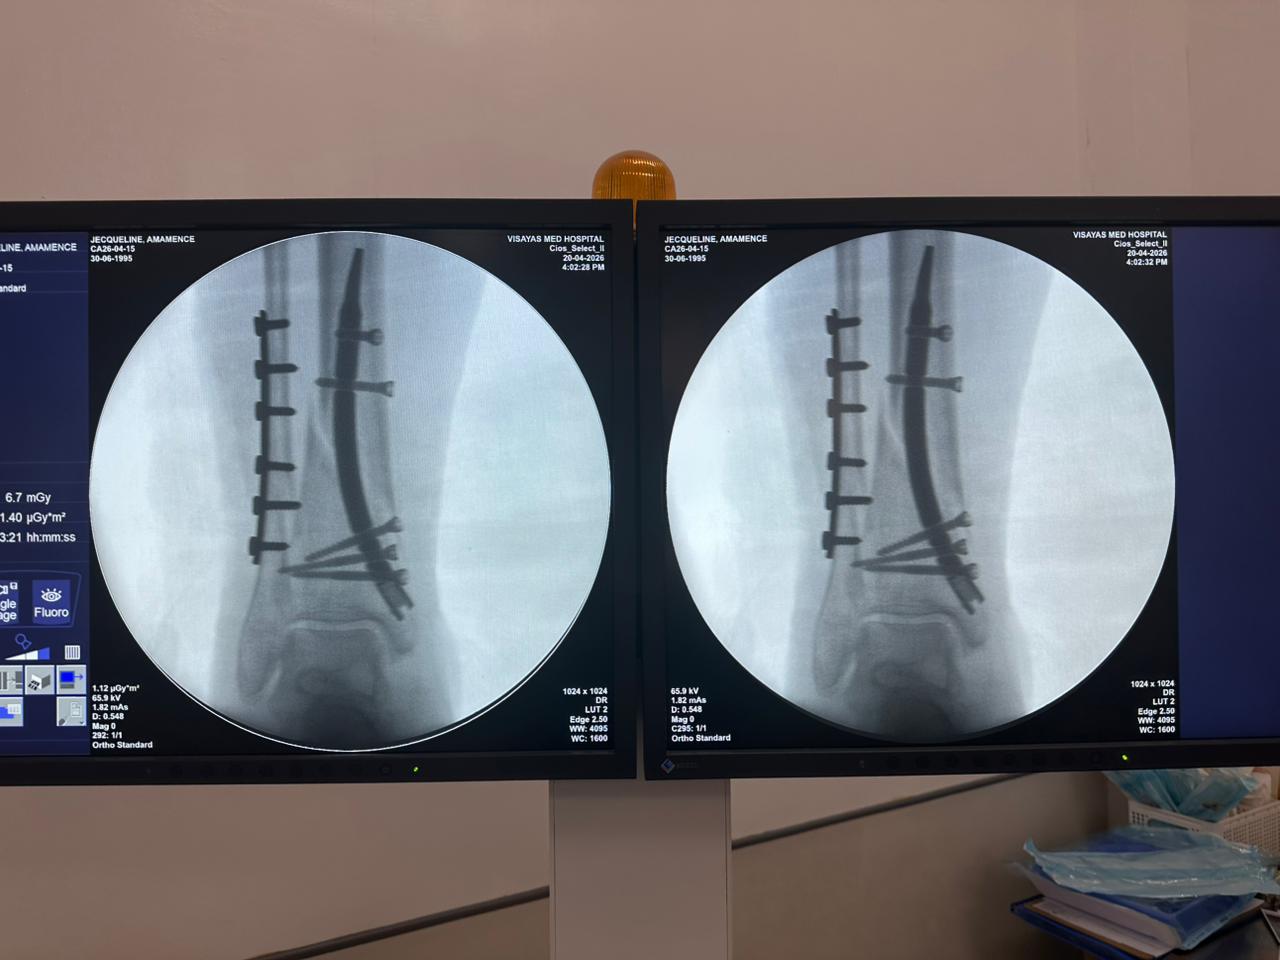

Étude de cas sur la fixation d'un clou tibial distal avec support de plaque fibulaire

Radioscopie peropératoire de l'arceau, vues AP et latérales

Ce cas concernait une fixation tibiale distale à l’aide d’un clou tibial distal intramédullaire. La radioscopie peropératoire a confirmé la position du clou, des vis de verrouillage distales et de la fixation par plaque fibulaire.